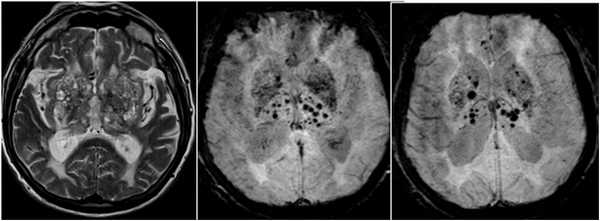

- Спорадическая болезнь мелких церебральных сосудов: Церебральная амилоидная ангиопатия

Церебральная амилоидная ангиопатия (САА) характеризуется наличием гомогенных эозинофильных отложений в кортикальных и менингеальных сосудах, что приводит к люминальным стенозам и фибриноидному некрозу. Это делает сосуды хрупкими и увеличивает тенденцию к кровотечению. Церебральная амилоидная ангиопатия не имеет корреляции с гипертонией, сахарным диабетом или атеросклерозом. При визуализации может быть представлена поверхностными лобарными гематомами, обычно с субкортикальным или субарахноидальным распространением. Фокальное или пятнистое / сливное поражение белого вещества (70%), и/или негеморрагическая диффузная энцефалопатия. GRE и T2 могут показать мультифокальные мелкие темные включения ( рис. 5 ).